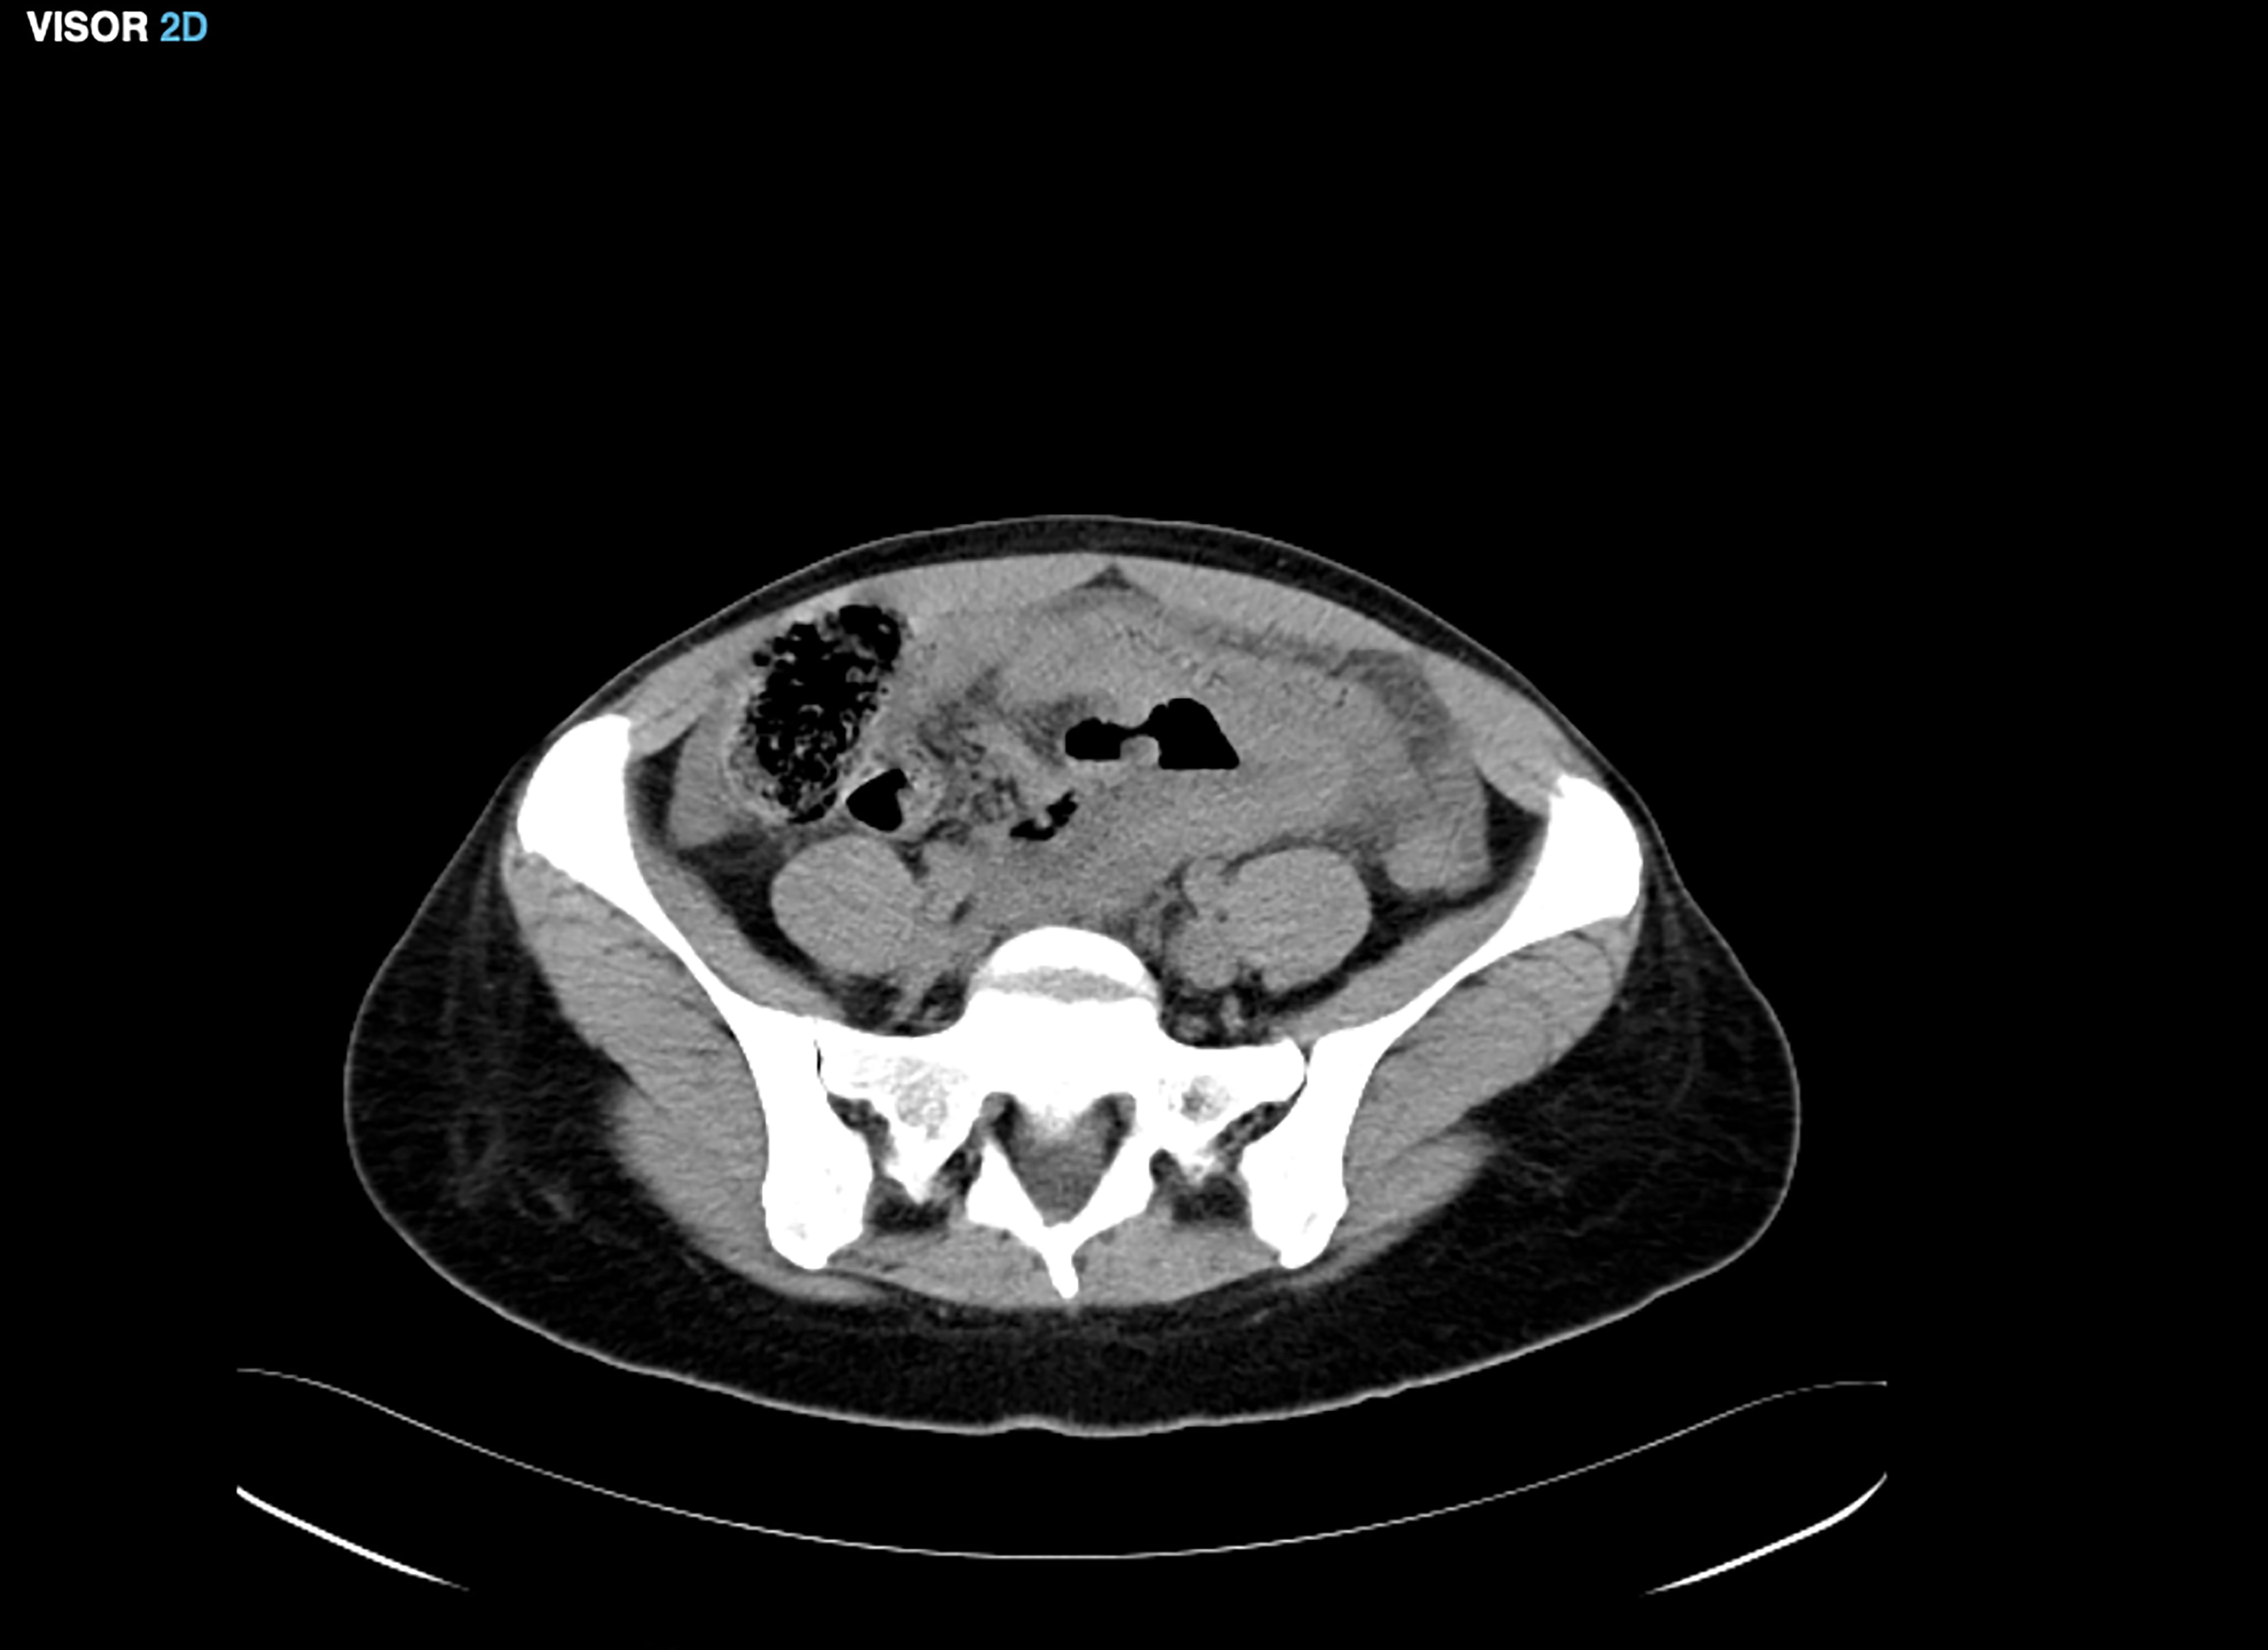

The patient came to the emergency department reporting intense abdominal pain and abdominal swelling for a month after having suffered a miscarriage at 6 weeks after a frozen embryo transfer performed at an external center. An emergency abdominal CT was performed, showing moderate ascites predominantly in the pelvic region (Fig. 2), which was initially treated with diuretics, albumin and anticoagulants.

Fig. 2.Moderate ascites in the pelvic region.

However, due to the poor clinical evolution of the patient, a culdocentesis guided by ultrasound was performed 4 days after her admission and 500 mL of peritoneal fluid was aspired and analyzed, being positive for chlamydia. The endocervical culture was also positive for chlamydia. Antibiotic treatment with doxycycline was initiated, and the patient was discharged 2 days after culdocentesis with relevant clinical improvement.